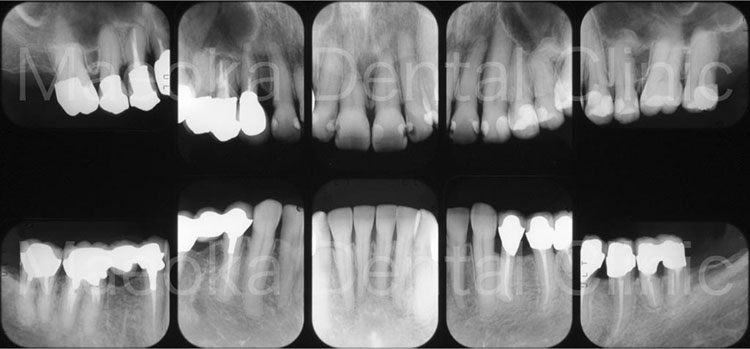

患者さんは49歳女性の方で、「全体的にしっかりと治したい」という主訴で来院されました。

出産を機にお口の環境が悪くなっていったとのことでしたが、勇気が出せずになかなか歯科を受診できなかったそうです。

診査を行うと奥歯の噛み合わせが失われており、審美面、機能面ともに大掛かりな介入が必要な状態でした。

はじめに患者さんから伺った情報を基に、現在の環境になってしまった根本的な原因を模索し、原因除去を行っていきました。その後、歯の移植(右下5を右上3に移植)、部分的な矯正などを行った上で審美的な範囲はセラミックスを用いた被せ物、歯の削除量を最小限にするために見えない箇所は金属を用いた被せ物で最終的な修復を行いました(一部表面的な虫歯は残っていますが、患者さんと相談した上で、今の段階で積極的に削ることは避け、経過観察を行うこととしています)。

プロビジョナルレストレーション(精密な仮歯)を入れた上で機能上問題ないことを確認するなどチェック期間にも時間を要したため、5年に及ぶ治療期間を要しましたが、残りの患者さんの人生の長さを考えると必要十分な治療であったと考えます。

保存不可能と思われる歯が多数ある中ではありましたが、結果として抜歯に至った歯は3本のみで、インプラントを用いることなく、患者さん自身の歯でお口の環境を再構築することができました。

今後はメインテナンスで治療終了時の環境を長期的に維持できるように努めていきます。

治療前(10枚法)

治療後(10枚法)